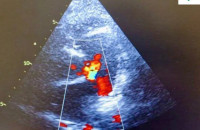

- Вроджені вади серця без міфів: розмова з лікарем Закарпатського кардіоцентру Вікторією Сабов ІНТЕРВ’Ю

- Серця під надійним контролем: Закарпатському кардіоцентру планують закупити новий ангіограф